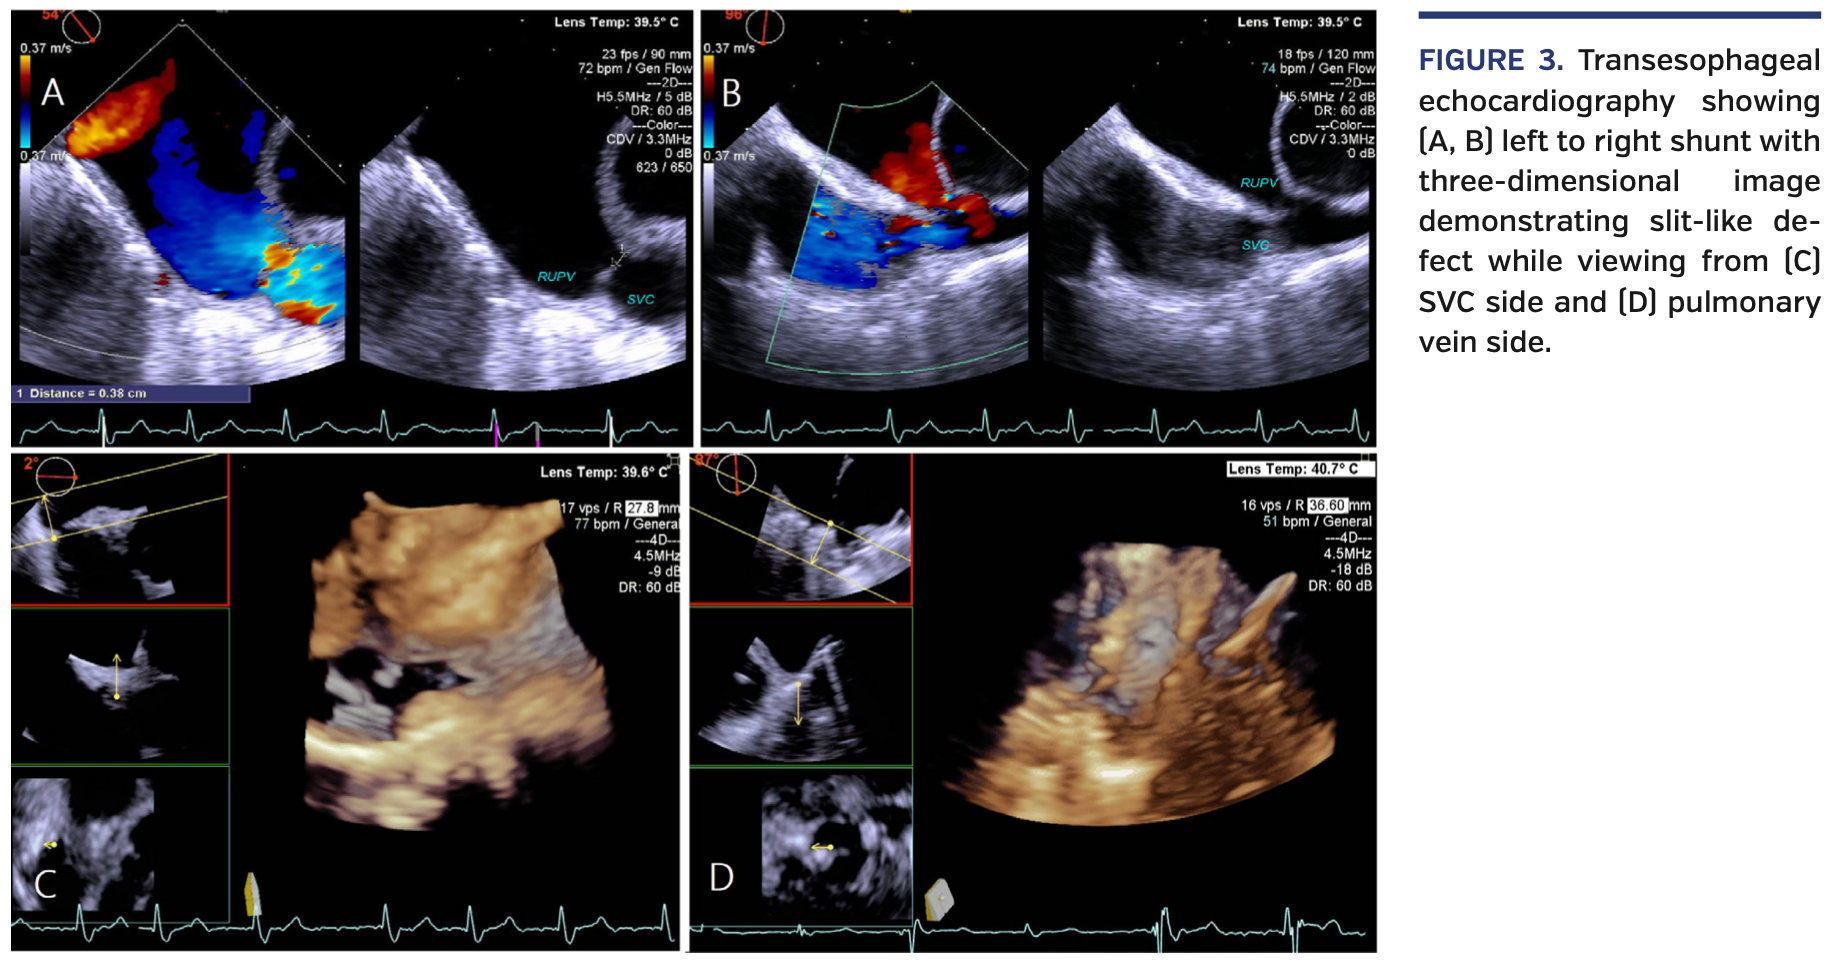

Computed tomography angiography (CTA) revealed partial anomalous pulmonary venous return (PAPVR) with dual drainage from right upper pulmonary vein (RUPV) to the distal superior vena cava (SVC) and left atrium (Figure 2). Given prohibitive surgical risks, we opted for a transcatheter approach. Under transesophageal echocardiography/fluoroscopy guidance, a 39 mm covered CP stent (B. Braun) was deployed at the distal SVC, successfully closing the left-to-right shunt (Figures 3 and 4; Videos 1-3). He had an uncomplicated hospital course and was discharged the next day.